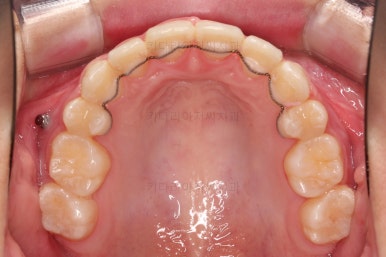

초진 시 입안의 모습입니다.

위아랫니가 많이 삐뚤진 않는데 뭔가 이상하죠?

어금니 맞물림은 지그재그로 잘 맞물려 있는데 위아래 앞니는 서로 앞뒤로 매우 멀죠.

비밀은 매우 자연스러워 보이지만 아래 앞니 2개가 선천 결손인 상태였습니다.

앞니끼리 맞물리지 않다보니 아래 앞니는 점점 솟구쳐 과개교합(깊게 맞물려 아래 앞니가 거의 보이지 않는 현상)이 되게 됩니다.